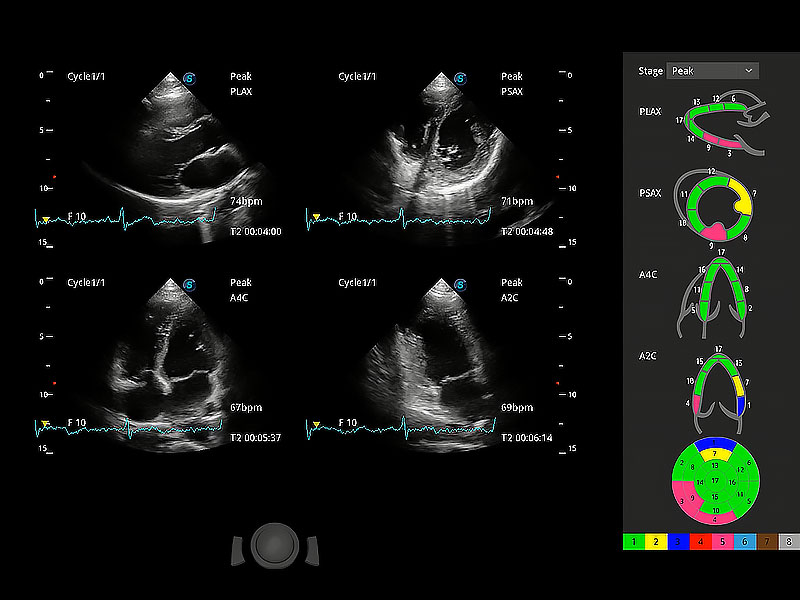

通過心肌識別技術(shù)與二維斑點追蹤技術(shù)相結(jié)合,對心臟的超聲圖像進行量化分析。計算心肌17個節(jié)段的應變、應變率、速度、位移等,并通過牛眼圖的形式進行呈現(xiàn)。

具備多種協(xié)議可選,同時支持17階段劃分法和專業(yè)的SE報告。